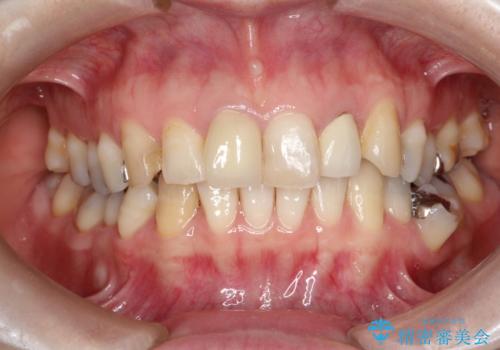

右上の1番目の歯の保険のかぶせ物と金属の土台を、ファイバーコアとオールセラミックにて再補綴する計画としました。

今回治療することで、自然な前歯になったと喜んでいただけました。